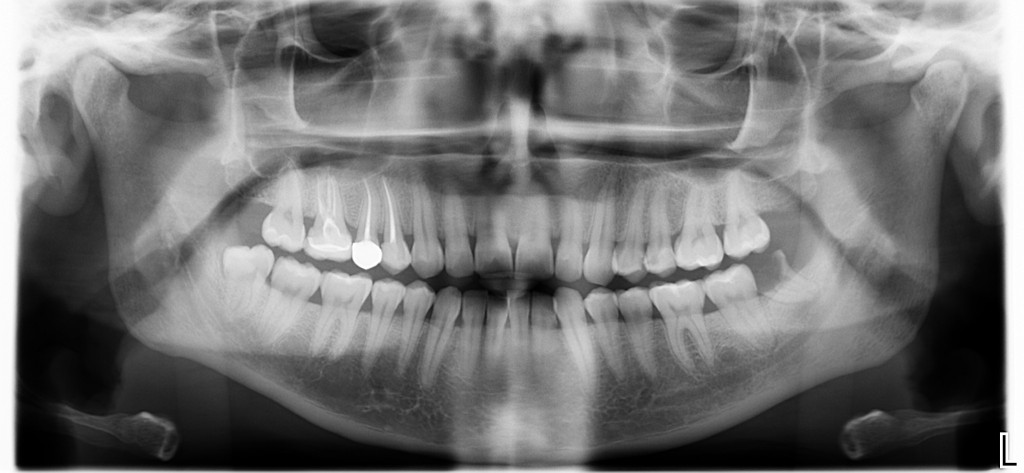

Per la quarta volta in due anni Angelica aveva male al 38. Un male da sbattere la testa contro il muro ma inspiegabilmente non lo aveva ancora tolto.

Ma ora torniamo alla mia esperienza odierna. In realtà Angelica mi ha raccontato che il vecchio dentista aveva provato a togliere il dente ma questo si era “rotto” durante l’estrazione e a quel punto è iniziata l’avventura.

Dopo dieci minuti da questo mio pensiero quello che restava del dente aveva abbandonato la bocca di Angelica e giaceva sul mio carrello chirurgico.

Accettando il fatto che le complicazioni operative succedono e ipotizzando che il collega possa aver avuto un buon motivo per non riuscire in prima seduta a togliere quel dente ?, perché io in dieci minuti ho tolto il dente alla povera Angelica mentre il collega non ci è riuscito in due anni?